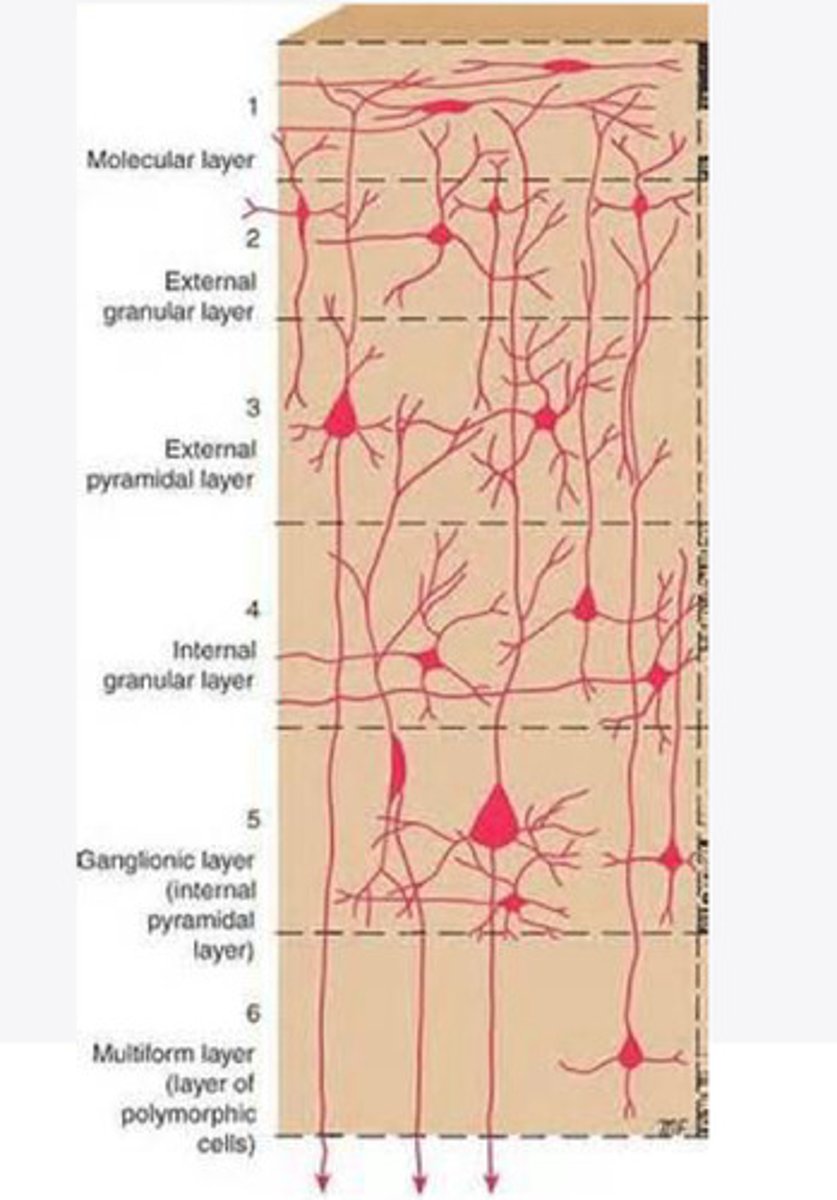

divided into 6 distinct layers, due to varying densities of cell body types within each layer

The cortex of the brain is divided into how many layers? Why is it divided into layers?

Layers of the cortex of the brain pic

2 and 4

What are the layers of the cortex that are associated with input?

3 and 5

What are the layers of the cortex that are associated with output?

molecular layer

What is the name of Layer 1 of the cortex of the brain?

very few cells

Does Layer 1 of the cortex have a lot or few cells?

receives dendrites from internal layers so it may actually function as a coordinating center where layers can communicate action

What does Layer 1 of the cortex do?

1

Every layer sends densities to Layer ____?

1

What layer serves as the "water cooler" of the brain?

external granular layer

What is the name for layer 2 of the cortex of the brain?

receives input from other cortical regions

What is the function of Layer 2 of the Cortex of the brain?

Stellate

What type of cells (stellate/pyramidal) would be most concentrated in Layer 2?

external pyramidal layer

What is the name for layer 3 of the cortex of the brain?

sends output to the other cortical layers

What is the function of Layer 3 of the cortex of the brain?

pyramidal

What type of cells (stellate/pyramidal) would be most concentrated in Layer 3 of the brain?

Layers 2 and 3

What layers are associated with association and commissural fibers?

Layer 3 - axons of cell bodies

Layer 2 - synapse into target areas in Layer 2

What part of the axons is in Layer 2/ in layer 3?

Layer 3 - external pyramidal layer

All axonal cel bodies for association and commissural fibers lie within what layer of the Cortex of the brain?

internal granular

** or called the striate cortex because it is so thick that you can see a line through this layer even in unstrained brain slides

What is the name for the 4th layer of the cortex of the brain?

receives input from the thalamus, geniculocortical layer, and other brainstem areas

What is the function for the 4th layer of the Cortex of the brain?

very thick within the vision, auditory, and somatosensory areas

Is Layer 4 thick or thin within SENSORY areas of the cortex?

Internal pyramidal

What is the name for Layer 5 of the cortex of the brain?

sends axons to the brainstem (corticobulbar) and spinal cord (corticospinal)

What is the function of Layer 5 of the cortex of the brain?

in motor areas of the cortex?

Where is layer 5 very thick in the brain?

the frontal lobe -- very motor heavy

What lobe of the brain will have a thick layer 5 of the cortex of the brain?

the multiform layer

What is the name of layer 6 of the cortex of the brain?

-sends axons back to the thalamus through corticogeniculate fibers

-modulates what information the thalamus sends to the cortex to control the strength of the signal received and modulate what you pay attention to

What is the function of layer 6 of the cortex of the brain?

no

Is layer 6 a motor layer?